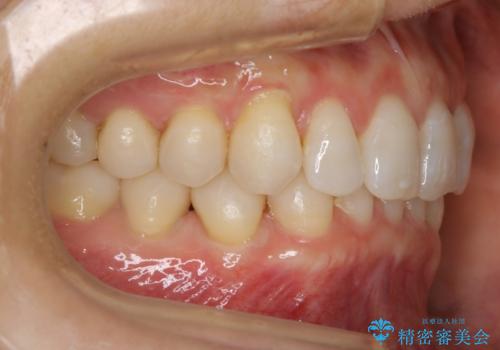

【抜歯】矯正治療とインプラントで正常な噛み合わせを実現

- 元々は矯正治療を主訴にご来院されました。

治療を始めるにあたり、精密検査を受けていただき全体の状況を把握したうえで矯正治療の計画を立てることとなりました。

その過程で左下の6番目の歯は治療が必要な状態であることが分かり、被せ物を外して内部を確認してみると根が破折してしまっていることが判明しました。

歯が深い位置で破折している場合は基本的には抜歯が選択されます。

様々な治療プランを患者さんと相談させて頂き、最終的にインプラントで噛み合わせを回復させていくこととなり、まず悪くなっている歯を抜歯することから開始しました。